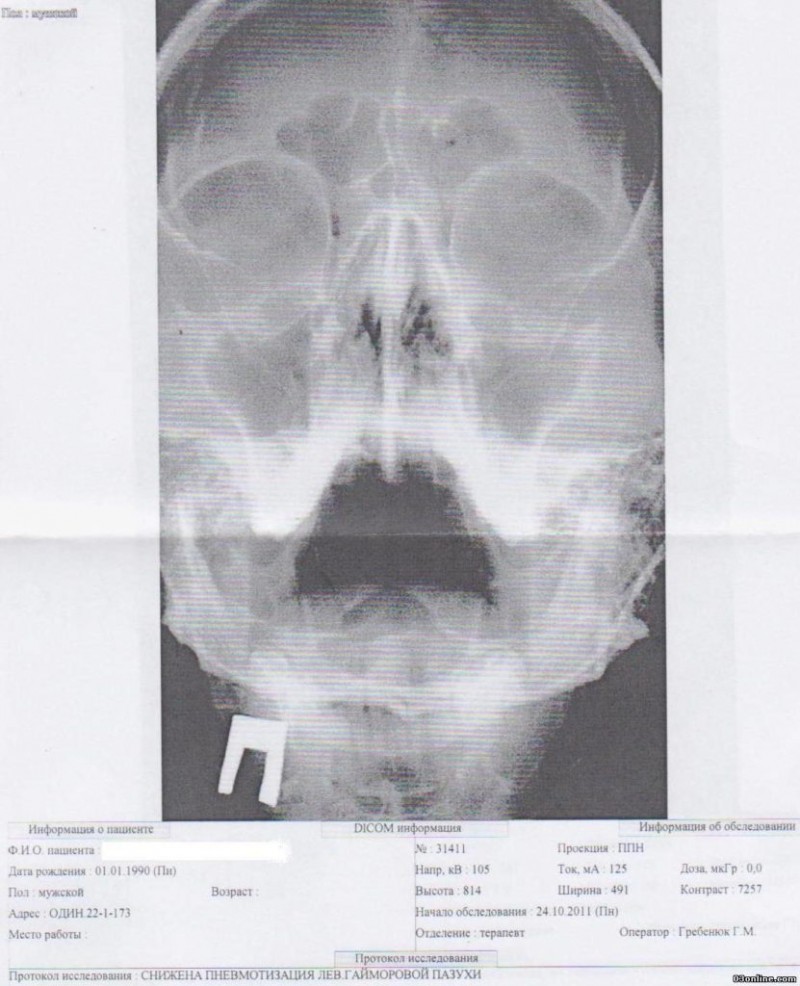

Однако точное определение заболевания возможно только после изучения рентгеновских данных. Пациенту проводят процедуру рентгенографии, и если присутствует гайморит, область между глазами и верхней челюстью будет иметь непрозрачный, белый оттенок.

Если в пазухах нет патологии, то на рентгене костные стенки будут иметь четкие контуры.

Рентгенологические признаки гайморита

При посещении пациентом с характерными признаками гайморита, врач обязательно назначает проведение рентгенографии в качестве дополнительного метода диагностики заболевания. Если в результате воспалительного процесса в гайморовых пазухах накапливается экссудат, на рентгеновском снимке это проявится в виде затемнений в области верхнечелюстных пазух.

При проведении рентгенографии гайморита можно заметить чёткий контраст между чёрными пазухами и белым инфильтратом, что часто называют симптомом «молока в стакане». Если рентгенолог видит этот симптом в двух проекциях, то диагноз гайморита подтверждается. При гнойном гайморите также наблюдается чёткое затемнение области гайморовых пазух при проведении исследования в боковой и прямой проекциях.

Если в полости носа есть жидкость, то на рентгенограмме будет видно затемнение. Врач может привести примеры рентгенограмм, чтобы проиллюстрировать этот факт. Он объясняет, что выявление гайморовых пазух не зависит от уровня или типа затемнения на снимке. Наличие затемнения не всегда означает наличие гайморита. Точно так же нельзя сразу определить наличие фронтита. Гайморит представляет собой воспалительное заболевание пазух носа, в которых может накапливаться различного вида жидкость.

Накопление гнойного материала в синусах при гайморите можно увидеть на изображении как светлое пятно на фоне темной полости. При значительном объеме содержимого можно разглядеть его горизонтальную линию.

Иллюстрация здоровых пазух напоминает темные полуовальные полости, расположенные по обе стороны от носа. Они имеют одинаковую окраску и соответствуют глазницам. Это свидетельствует об отсутствии любых патологий. Появление даже маленьких светлых областей будет указывать на начало воспалительных процессов. Чем сильнее воспаление, тем ярче белые пятна. Кроме того, изображение носовых пазух изменится. При гайморите на рентгеновском снимке пазухи носа будут иметь неровные контуры и утолщенные стенки.

При осуществлении диагностики врач проводит осмотр и оценку состояния решетчатой кости. Гайморит способен вызвать распространение воспаления в верхнечелюстные гайморовы пазухи. В них может накапливаться жидкость различного типа: катаральная, слизистая или гнойная. На рентгеновском снимке она будет заметна как светлое пятно с четкими контурами на фоне темной носовой пазухи.